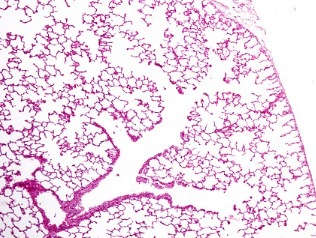

¿Qué te dice esto?

Patrón característico de neumopatía intersticial usual.

Patrón histológica Neumopatía intersticial usual

Panal de abeja